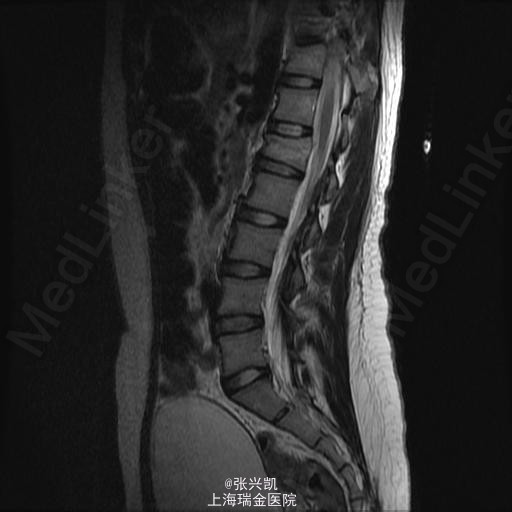

检查:腰背部叩痛,压痛明显,脊柱无侧弯,双下肢肌力及感觉正常,膝腱反射等存在,巴氏征(-)。 辅助检查:X线平片示:T11,L椎体骨折 头颅CT及肋骨CT示:T11椎体,左侧横突及椎弓,及L1椎体骨折 MR:T11,L1椎体新鲜骨折

诊断:多发胸腰椎骨折(T11,L1) 处理:胸腰椎骨折经皮椎弓根钉复位内固定术,一年后骨折愈合良好,行内固定装置取出术